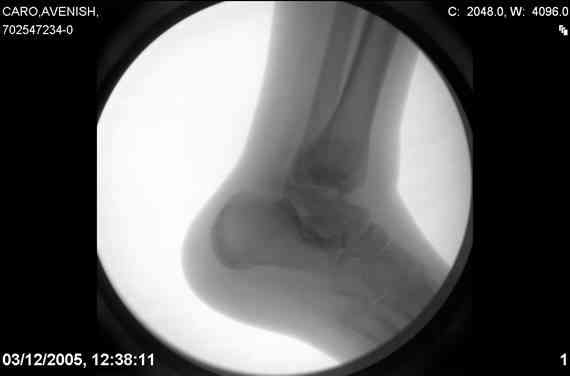

ya by popytalsya sobrat talus anatomichno,seichas pozdno operirovat iz za oteka,po etomy distrakziya apparatom budet optmalna.Posyalu vam podobyai moi sluchai.

14 years old girl

Fall from height ( 3rd floor)

Compressed fractures of L1-L2

Fx of orbital bone

Mark, судя по снимкам в день поступления произведен А.В.Ф., а остеосинтез ч-з какое время произведен?, остеосинтез произвели открытым способом?( на снимке п/о рубцы).

aparat postavlen v den postupleniya,rastaynuli, vpravili zakryto naskolko vozmoghno, a kogda otek spal sdelali otkrytoe vpravlenie.Teryat tut nechego, moghno tolko uluchshit.